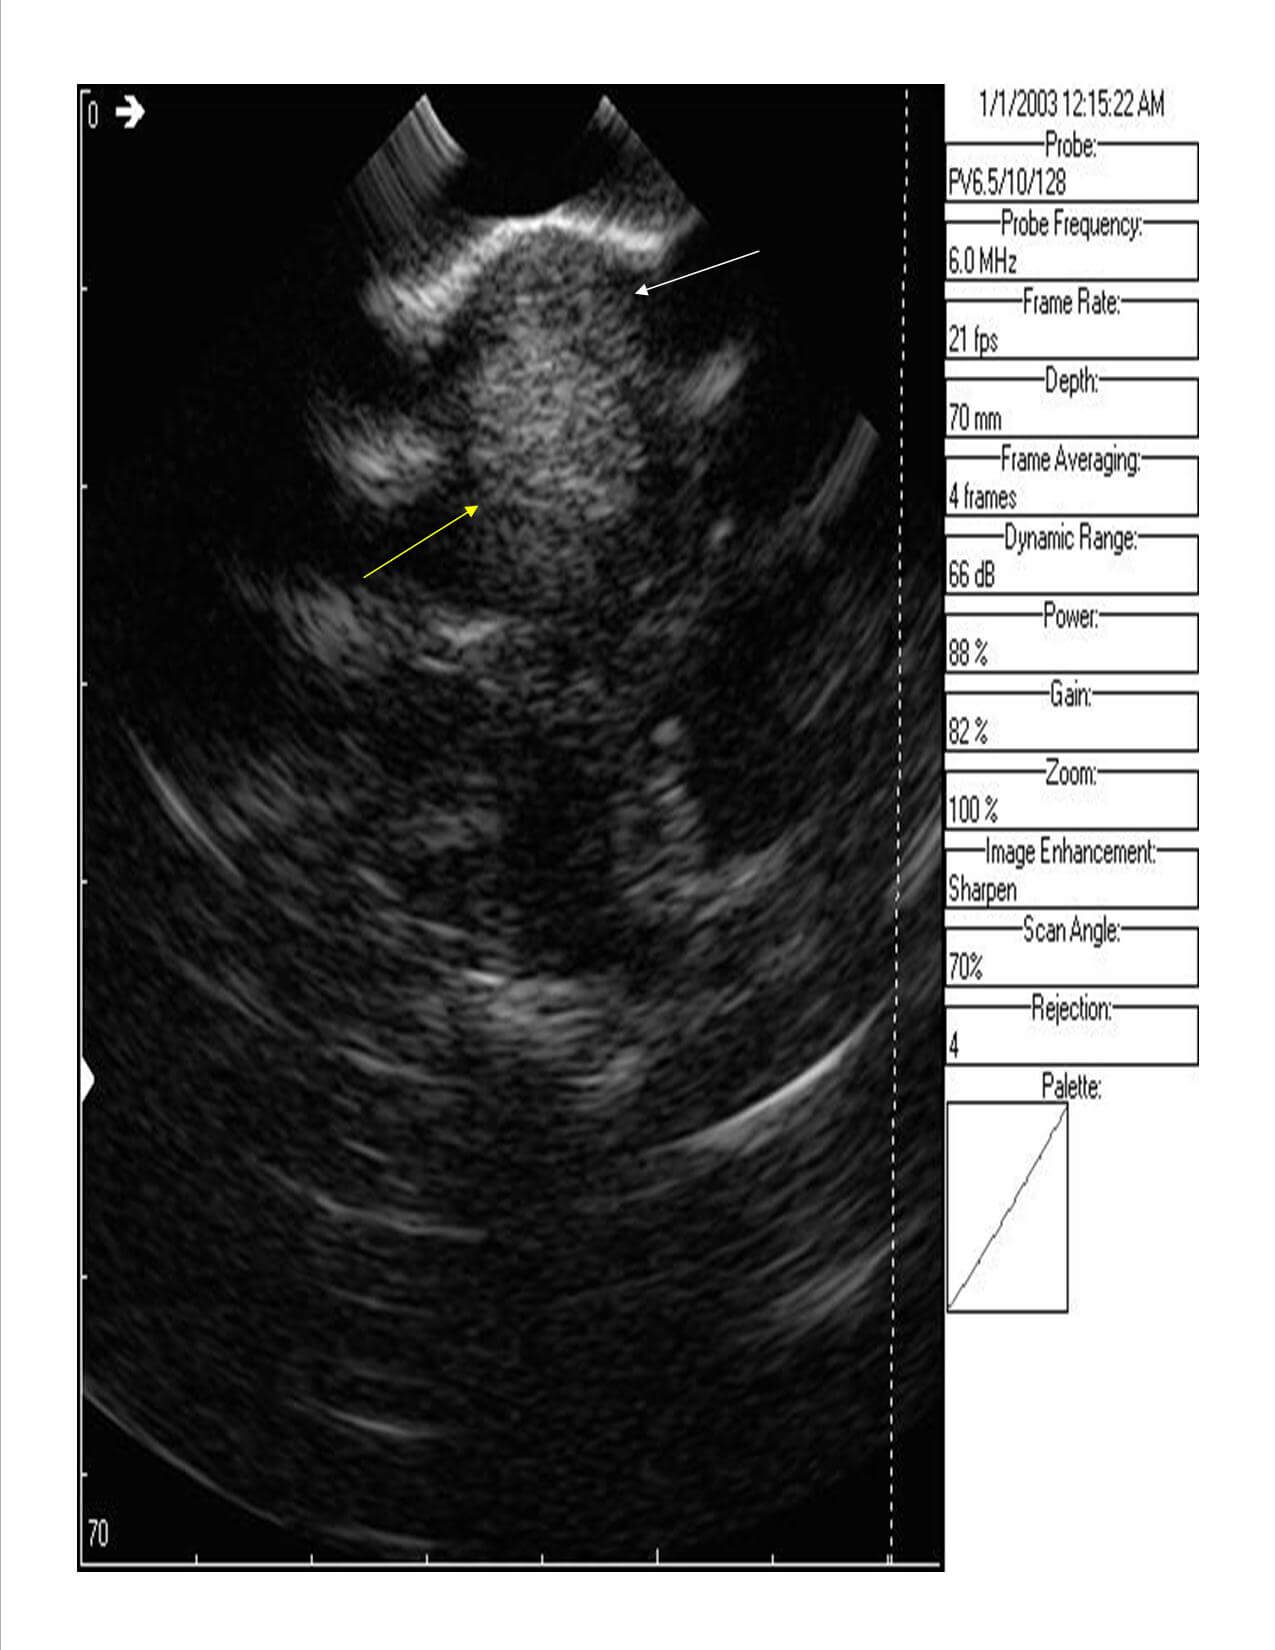

Here are some ultrasound images but in order to know abnormal, we first must know normal. The image to the left is of this horse’s normal left front tendon region, demonstrating normal anatomy and sizes of the flexor tendons just above the fetlock region. The white arrow demonstrates the superficial flexor tendon, which is a comma shaped structure, essentially overlapping or wrapping around the deep flexor tendon from the 11 o’clock to the 2 o’clock position. The deep flexor tendon, which is the yellow arrow, and a more circular type structure. Both tendons are viewed on cross section. There is a small black central area to the superficial flexor tendon here in the ‘normal’ leg, which may be a central area of injury that has occured in the left fore as well.

The image to the right is the same region on the right front, which is the injured limb. By comparing the two images, we can see that the superficial flexor tendon on the right fore is dramatically enlarged with a central black region, which is a core lesion. The overall enlargement is likely due to scarring or fibrosis within the tendon, but we can appreciate that the superfiical flexor tendon in the right front is so large that it is wrapping around the deep flexor from about the 10 o’clock to the 5 o’clock position.

If we measure the circumferance of the superficial flexor tendon on the right front, it is approximately 97.0 mm with the central core (black) lesion being about 19.9 mm.